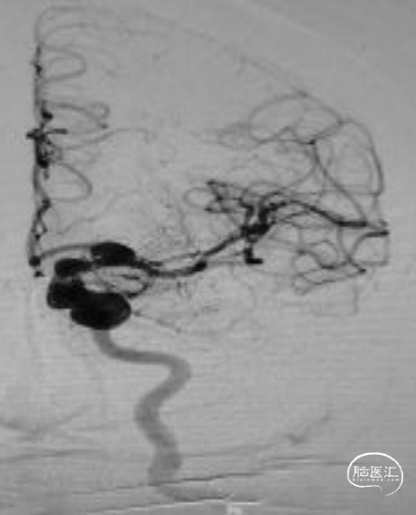

正位造影:

造影所示:患者左侧颈内动脉分叉部动脉瘤,大小约11mm*10mm,合并左侧颈内动脉终段、海绵窦段和岩骨段蛇形动脉瘤。动脉瘤形态复杂、不规则、体积大且长。大脑前动脉和大脑中动脉从分叉部动脉瘤上发出,压颈无代偿,采用微导管保护下瘤内扰流装置是比较理想的治疗策略。其近端蛇形动脉瘤,采用桥接血流导向装置能够达到较好的治疗效果。且已有研究表明,血流导向装置联合瘤内扰流装置治疗颅内复杂大型动脉瘤在技术上是可行的,且可能尽早地将动脉瘤闭塞。因此,经全科慎重讨论,本案例采用桥接血流导向装置+瘤内扰流装置植入术的治疗方案。